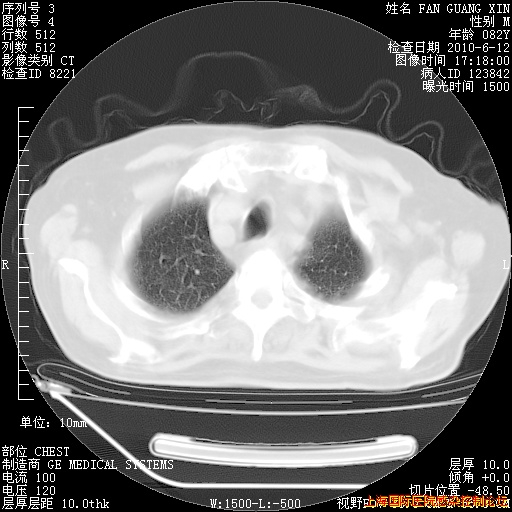

6月12日纵膈窗

补发6月12日肺部CT肺窗

6月12日肺窗